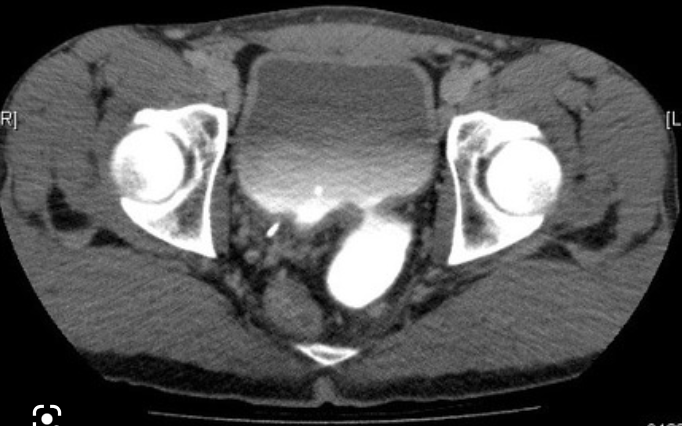

Q

A

Bladder ears (“transitory exztraperitoneal herniation of the bladder” into the inguinal canal

Note: This is a transient finding during Valsalva and often associated with inguinal hernias.